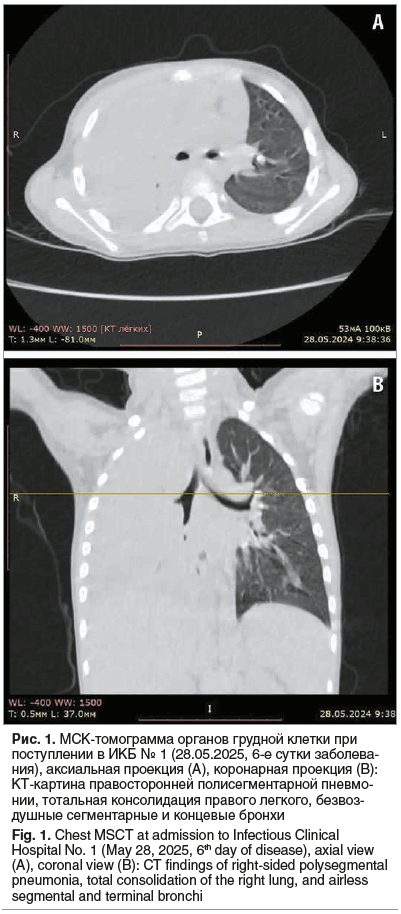

Инструментальные исследования: по данным мультиспиральной компьютерной томографии (МСКТ) органов грудной полости (ОГП) визуализирована правосторонняя полисегментарная пневмония (рис. 1).

На рентгенограмме ОГП картина правосторонней полисегментарной пневмонии. При УЗИ ОГП 28.05.2024 (6-е сутки заболевания) — правое легкое тотально безвоздушно, паренхима верхней и средней долей значительно диффузно изменена с неравномерным повышением эхогенности. Воздушная бронхограмма отсутствует. Эхопризнаки выпота в правой плевральной полости. Выявленные признаки свидетельствуют о высоком риске развития деструкции.